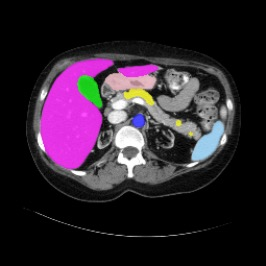

Integrating high-level semantically correlated contents and low-level anatomical features is of central importance in medical image segmentation. Towards this end, recent deep learning-based medical segmentation methods have shown great promise in better modeling such information. However, convolution operators for medical segmentation typically operate on regular grids, which inherently blur the high-frequency regions, i.e., boundary regions. In this work, we propose MORSE, a generic implicit neural rendering framework designed at an anatomical level to assist learning in medical image segmentation. Our method is motivated by the fact that implicit neural representation has been shown to be more effective in fitting complex signals and solving computer graphics problems than discrete grid-based representation. The core of our approach is to formulate medical image segmentation as a rendering problem in an end-to-end manner. Specifically, we continuously align the coarse segmentation prediction with the ambiguous coordinate-based point representations and aggregate these features to adaptively refine the boundary region. To parallelly optimize multi-scale pixel-level features, we leverage the idea from Mixture-of-Expert (MoE) to design and train our MORSE with a stochastic gating mechanism. Our experiments demonstrate that MORSE can work well with different medical segmentation backbones, consistently achieving competitive performance improvements in both 2D and 3D supervised medical segmentation methods. We also theoretically analyze the superiority of MORSE.